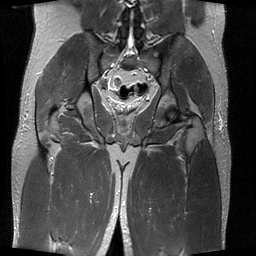

To simulate various input noise levels, several values for have been selected in the range . The set of high-quality magnitude MR test images used is shown in Fig. 6, and may be obtained from http://bigwww.epfl.ch/luisier/MRIdenoising/TestImages.zip.

| Image 1 | Image 2 | Image 3 | Image 4 |

|---|---|---|---|

![]() |